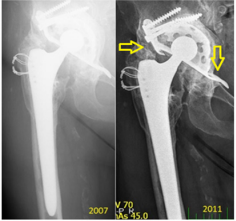

The migration occurred proximally, with breakage of the proximal screws and migration of the plate (from 2009). Then, a mixture of the screws is seen in the bottom of the joint space (2010) and luxation (2012). In the same year (2012), we re-admitted the patient for re-reimplantation and implanted a hemispheric modulus with excenter and larger revision stem. In Figure 6, a case of mechanical loosening of the BS plate is presented. This event does not, generally, lead to positional plate loosening. Instead, the plate protrudes into the pelvis slightly, though it is still capable of full-weight bearing.

Figure 6: Representative case of mechanical loosening of the BS plate involving the proximal region. No BS plate failure occurred in such a case. Yellow arrows denote the stability of the implant at 4-year post-implantation.